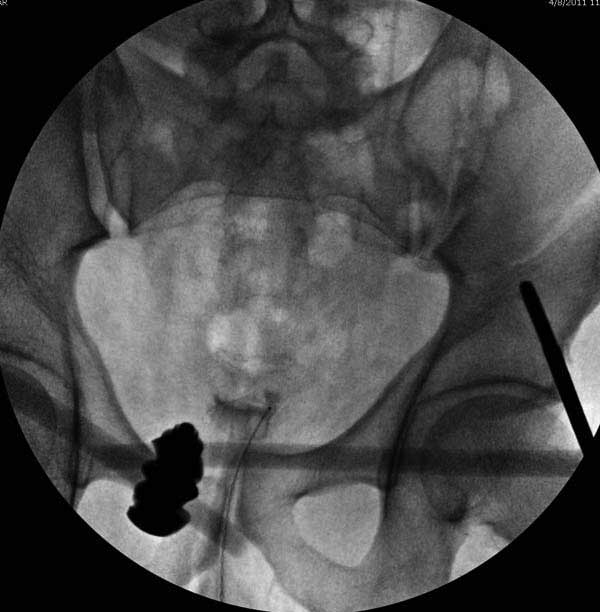

Здесь представлен случай 38 летнего больного (падение с высоты 9 метров) с нарушением тазового кольца. При поступлении для стабилизации передне-нижний аппарат наружной фиксации и на 6й день, вчера, операция из двух доступов.

Представлены снимки техники проведения стержней. Через место прикрепления прямой мышцы в Inferior Iliac Spine в направления вырезки создается жесткость. Weber clamp изнутри таза для репозиции, и фиксация после репозиции перелома крыла подвздошной кости. Наружный аппарат удален, нагрузка предполагается через два месяца.